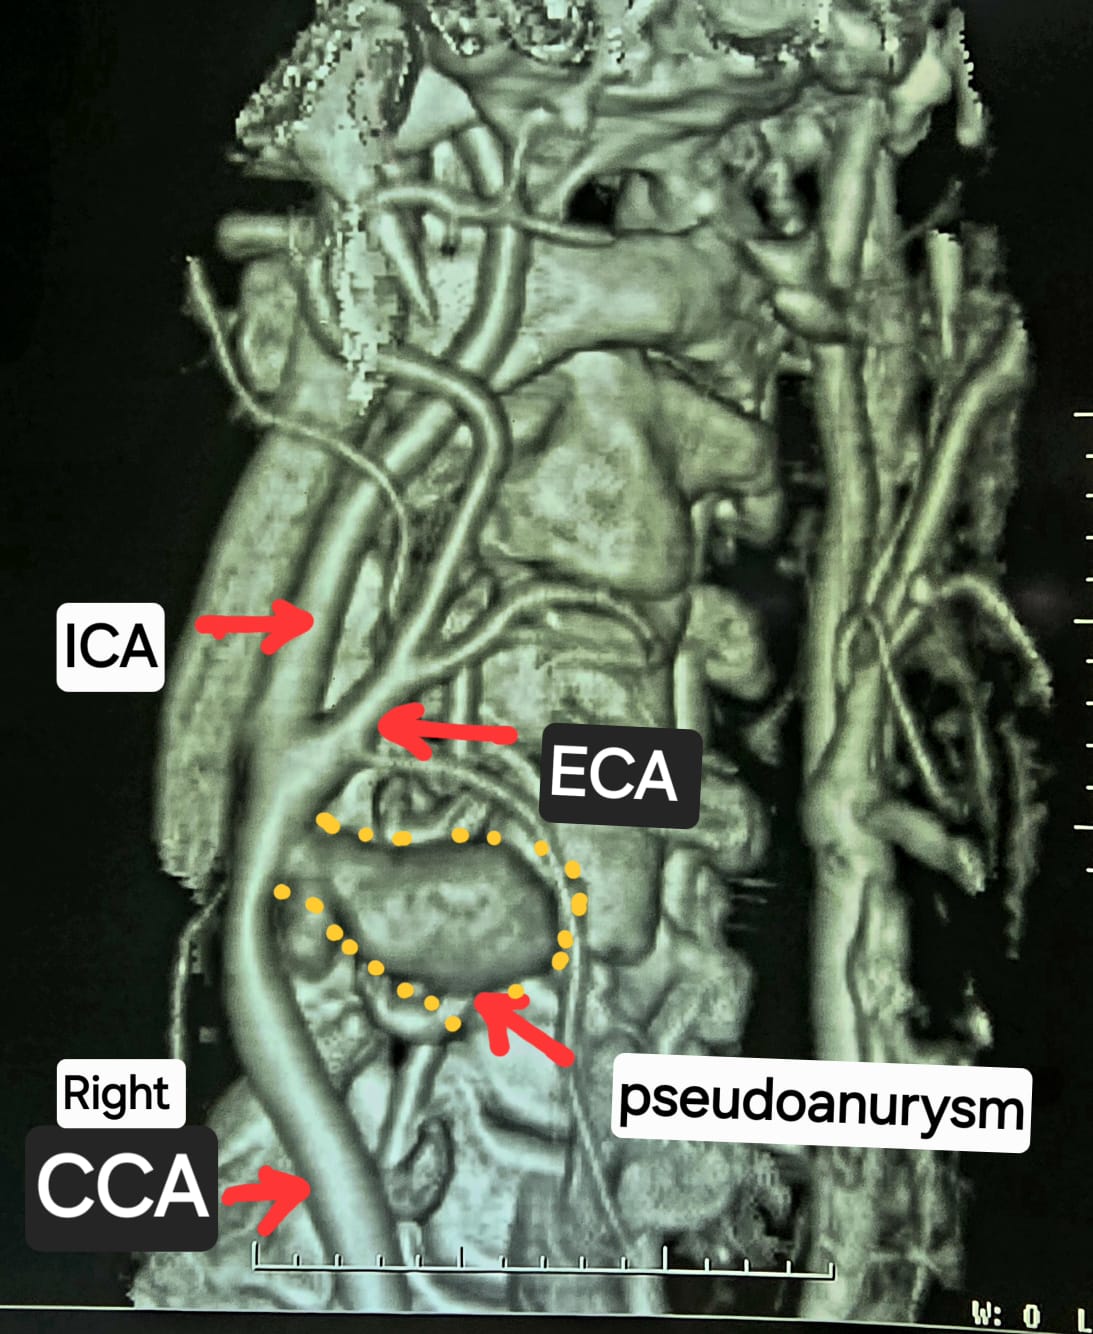

जानकारी के अनुसार, रायपुर के रहने वाले 40 साल के एक दुकानदार सुबह उठने के बाद घर में टूथब्रश कर रहे थे, इस दौरान उन्हें अचानक गले में तेज दर्द हुआ, देखते ही देखते पूरी गर्दन में सूजन आ गई और फिर वह बेहोश हो गए. परिजन उन्हें तत्काल अम्बेडकर अस्पताल के आपातकालीन विभाग लेकर पहुंचे, जहां गर्दन की नसों की सीटी एंजियोग्राफी जांच की गई, जिसमें पता चला की मरीज की दाई कैरोटिड आर्टरी फट गई है और उसके चारों ओर गुब्बारानुमा संरचना बन गई है, जिसे कैरोटिड आर्टरी स्यूडोएन्युरिज्म (Carotid Artery Pseudoaneurysm) कहा जाता है. गंभीर हालत को देखते हुए मरीज को हार्ट, चेस्ट एवं वैस्कुलर सर्जरी विभाग में रेफर किया गया. विभाग के एचओडी डॉ. कृष्ण कांत साहू की टीम ने ऑपरेशन कर उनकी जान बचा ली.

गर्दन की रक्त वाहिकाओं की सीटी एंजियोग्राफी में दाईं कॉमन कैरोटिड आर्टरी के बाइफरकेशन पर स्यूडोएन्यूरिज्म दिखाई दे रहा है.